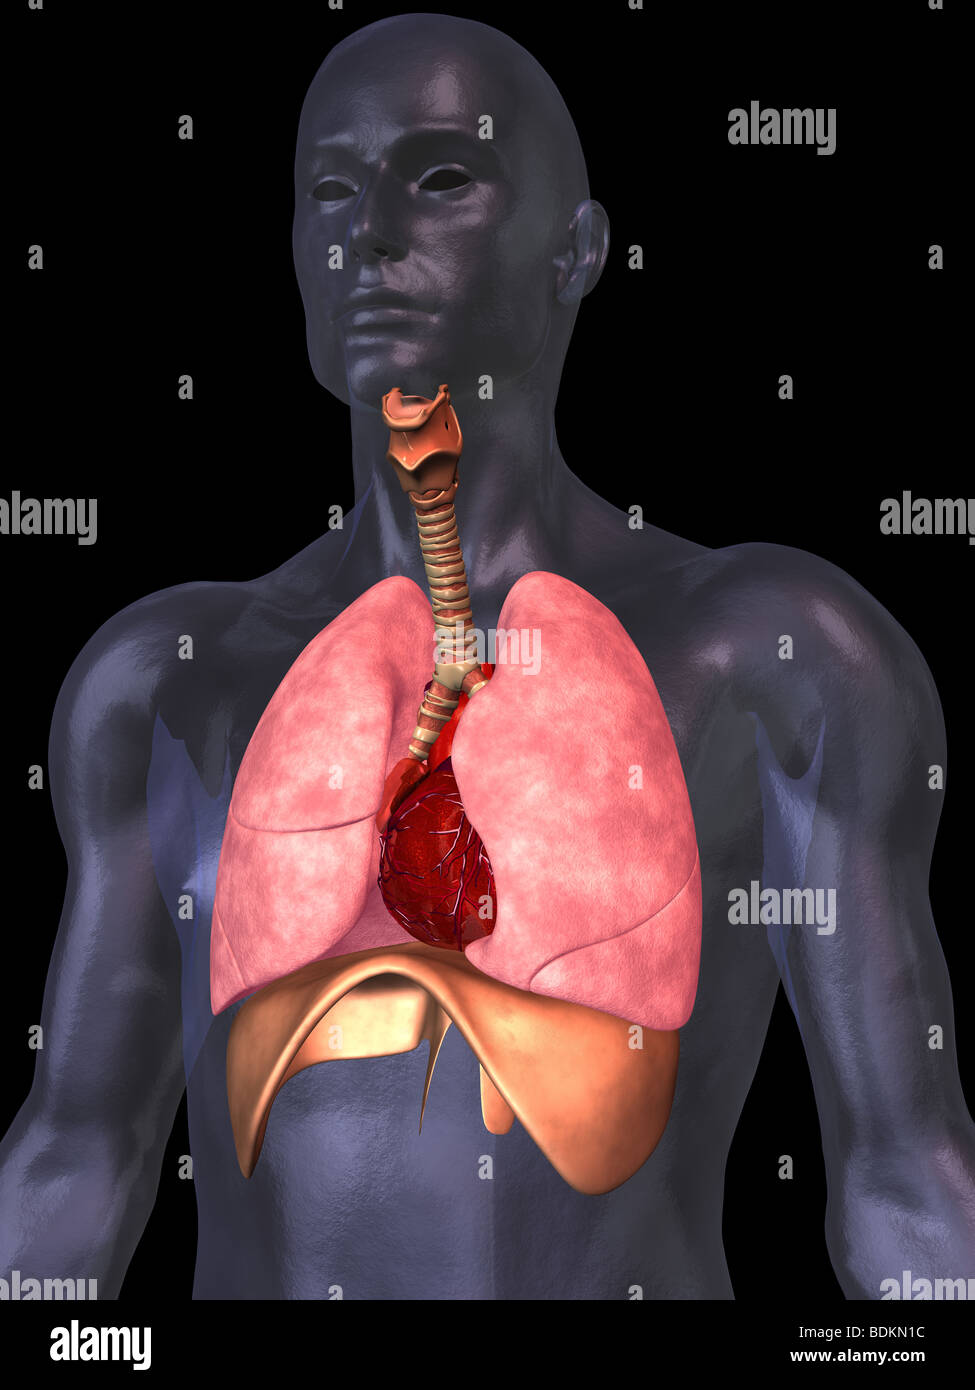

RFDGYRD7–Männliche Anatomie, inneren Organe allein, volle Atmungs- und Verdauungssystem, mit einigen Organen Cutaway. Anatomie-Bild.